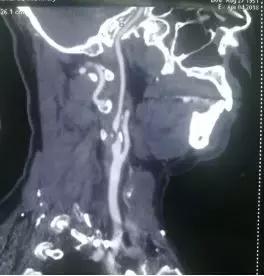

术前CTA影像检查